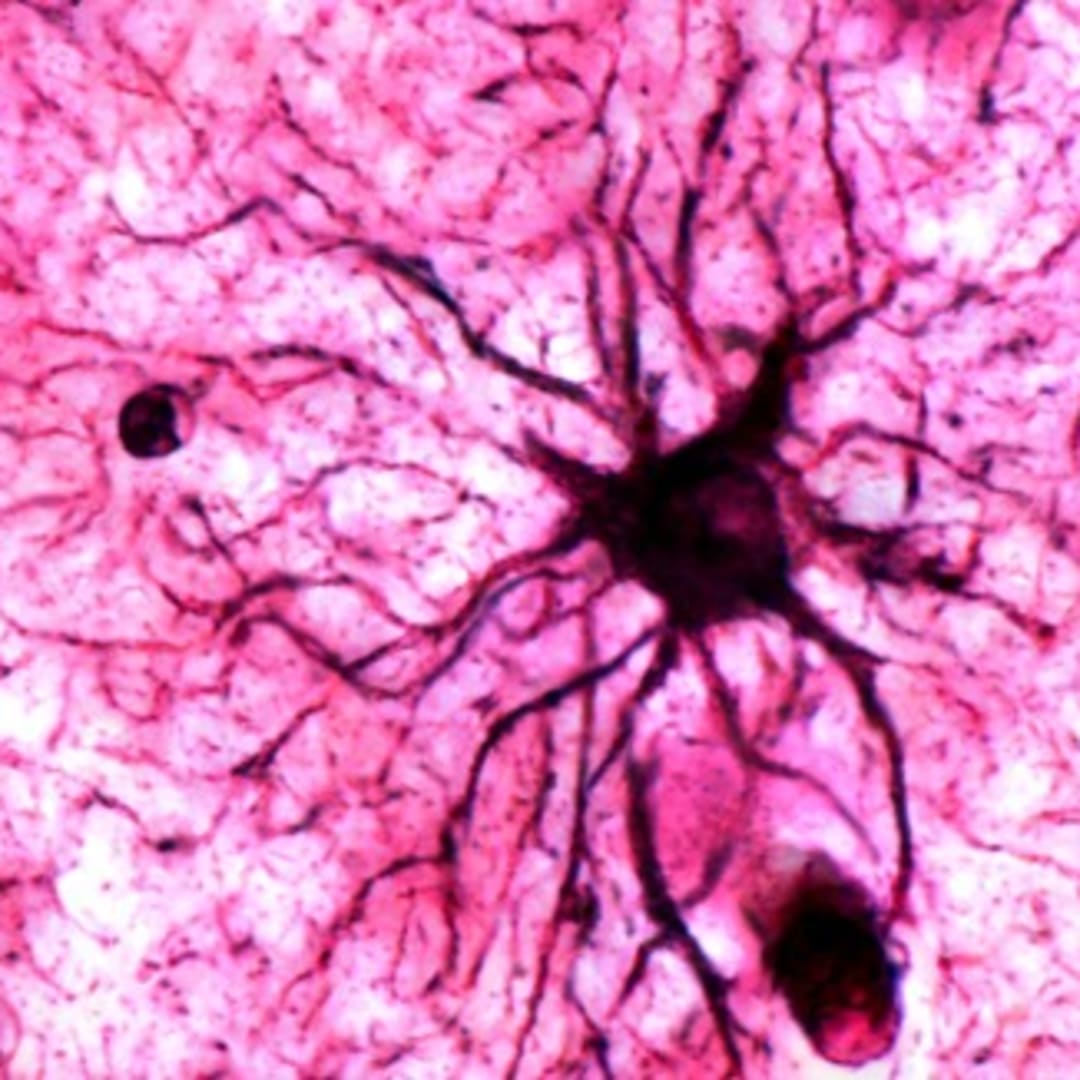

Courtesy of NatureMagazine

Wako, Jepang - Kenangan tentang peristiwa emosional seringkali lebih mudah diingat dibanding kenangan biasa. Sebuah studi terbaru mengungkap bahwa sel otak bernama astrocytes berperan penting dalam menstabilkan ingatan jangka panjang tersebut.

Sebelumnya, astrocytes dianggap hanya sebagai pendukung neuron yang menyimpan memori. Namun penelitian ini menunjukkan astrocytes aktif dipicu oleh pengalaman emosional yang berulang dan berkontribusi pada penguatan memori.

Sel astrocytes terutama aktif di area otak seperti amygdala, yang sangat terkait dengan pengolahan emosi dan memori ketakutan, memberi gambaran bagaimana memori penting disaring dan disimpan secara selektif.